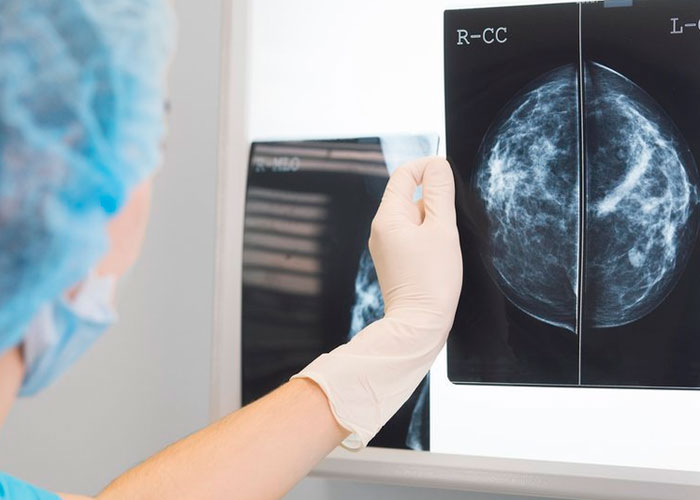

El nuevo método para detectar el cáncer de mama que puede ayudar a los médicos implica el uso de inteligencia artificial al examinar las mamografías y es capaz de determinar si el paciente está enfermo. Probado por científicos alemanes quienes compartieron el resultado en ‘The Lancet Digital Health’.

La investigación compara directamente el uso de una inteligencia artificial para la detección de este tipo de cáncer y determinó que la fórmula más efectiva para detectar correctamente los tumores es combinando las tareas del radiólogo con la tecnología.

En su experimento, los científicos demostraron que, ambos por separado, tienen peores resultados que si trabajan en equipo.

De hecho, analizando juntos, inteligencia artificial y radiólogo, las radiografías, los resultados a la hora de detectar el cáncer de mama son un 3,6 % mejores que un médico trabajando solo. Además, el trabajo en equipo provocó menos falsas alarmas.

Además de esta ventaja, trabajar con dichos sistemas de inteligencia artificial podría ayudar a salvar vidas al detectar cánceres que los médicos pasan por alto; así como liberar la carga de trabajo de radiólogos que, según ‘Technology Review’, no se dan cuenta de uno de cada ocho cánceres que ven en las radiografías.

Inteligencia artificial que es capaz de detectar más rápido el cáncer de mama

El software de inteligencia artificial que se está probando en Alemania ha sido desarrollado por Vara, una startup con sede en Alemania. Esta herramienta ya se utiliza en más de una cuarta parte de los centros de detección de este tipo de cáncer en Alemania. Además de usarse en un hospital de México y otro de Grecia.

Para enseñarle a detectar el cáncer de mama, los científicos de Vara proporcionaron a la inteligencia artificial con más de 367 mil 000 mamografías, incluyendo las notas de los radiólogos, evaluaciones e información sobre el paciente. A continuación, la IA debía colocar cada radiografía en un apartado: «seguro normal», «sin confianza» y «cáncer seguro».

Después, las mamografías etiquetadas por la inteligencia artificial como ambiguas o «cáncer seguro» se derivaron a un radiólogo para su posterior análisis. Esto se debe a que el entrenamiento de la IA es difícil, puesto que los senos sanos o cancerosos suelen tener cierto parecido.